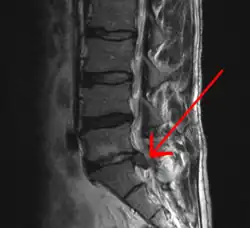

Imagem de RNM de hérnia de disco lombar (seta)

Hérnia de disco/hérnia discal é a projeção da parte central do disco intervertebral (o núcleo pulposo) para além dos seus limites normais (a parte externa do disco, o ânulo fibroso). Ocorre geralmente póstero-lateralmente, em virtude da falta de ligamentos que sustentem o disco nessa região.[1]